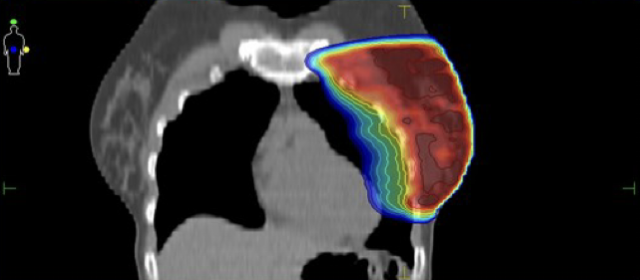

Πραγματοποιείται ακτινοβόληση σε καθορισμένη φάση της αναπνοής κατά την οποία αυξάνεται η απόσταση της καρδιάς από τον μαζικό αδένα μειώνοντας και τον όγκο του πνεύμονα ο οποίος ακτινοβολείται.

Κατανομή δόσης με την τεχνική ABC

Ελαχιστοποίηση δόσης στην καρδιά και τον πνεύμονα